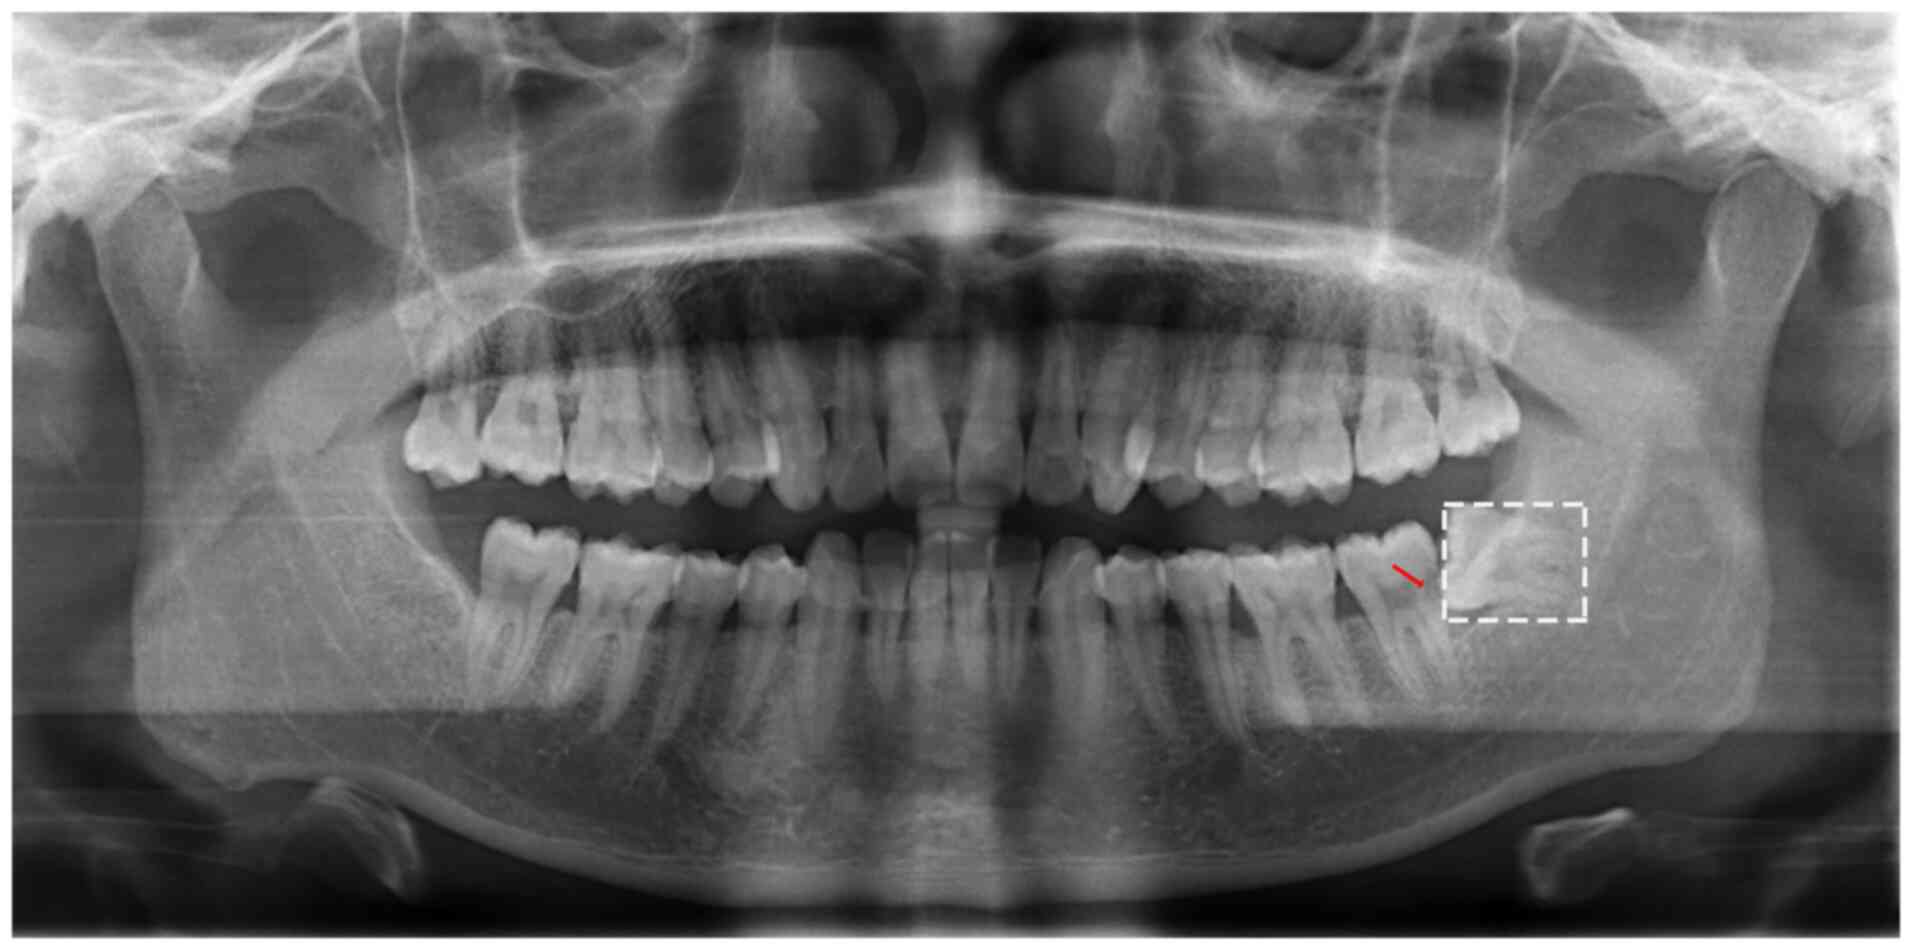

Persistent trismus following mandibular third molar extraction and its management: A case report and literature review

Trismus is one of the common complications which occur following the extraction of mandibular impacted third molars. This generally occurs due to low‑grade infection, repeated muscle stimulation, as well as other causes. This symptom is usually relieved after 1 to 2 weeks; however, it may persist for >1 month post‑operatively in very rare cases. The present study reports the case of a patient with trismus at 45 days following mandibular third molar extraction. The patient received local and systemic anti‑inflammatory treatment, combined with incision and drainage therapy under local anesthesia. In the present study, an analysis of the factors associated with the occurrence and development of trismus is also included, as well as appropriate management strategies in order to provide an effective treatment method for affected patients and for the prevention of trismus in the future.

Figure 1

Figure 2

Figure 3

Figure 4

Figure 5